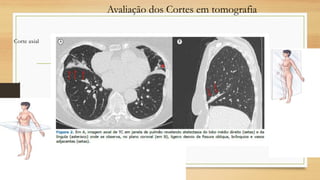

Avaliação dos Cortes em tomografia

Corte axial

Corte sagital

Corte coronal

Avaliação dos Cortesem tomografia Corte axial Corte sagital Corte coronal

Avaliação dos Cortesem tomografia Corte axial Corte sagital